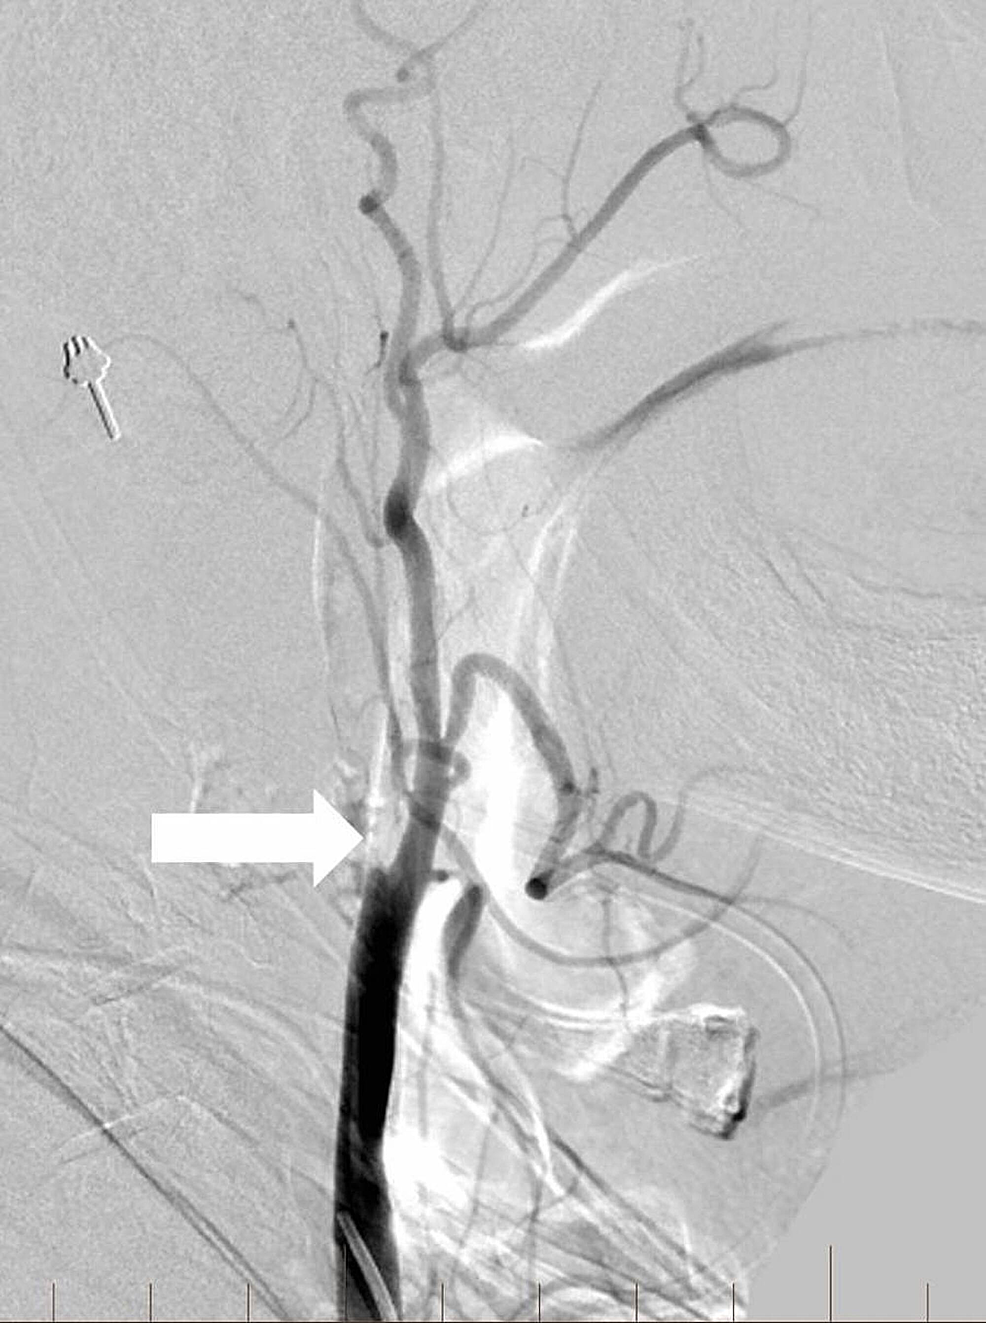

tPA was administered intravenously, and the patient was transferred to the interventional neuroradiology suite. Biplane digital subtraction angiography revealed a complete occlusion of the cervical right ICA at the vessel’s origin due to extensive atherosclerotic disease (Figure 6).